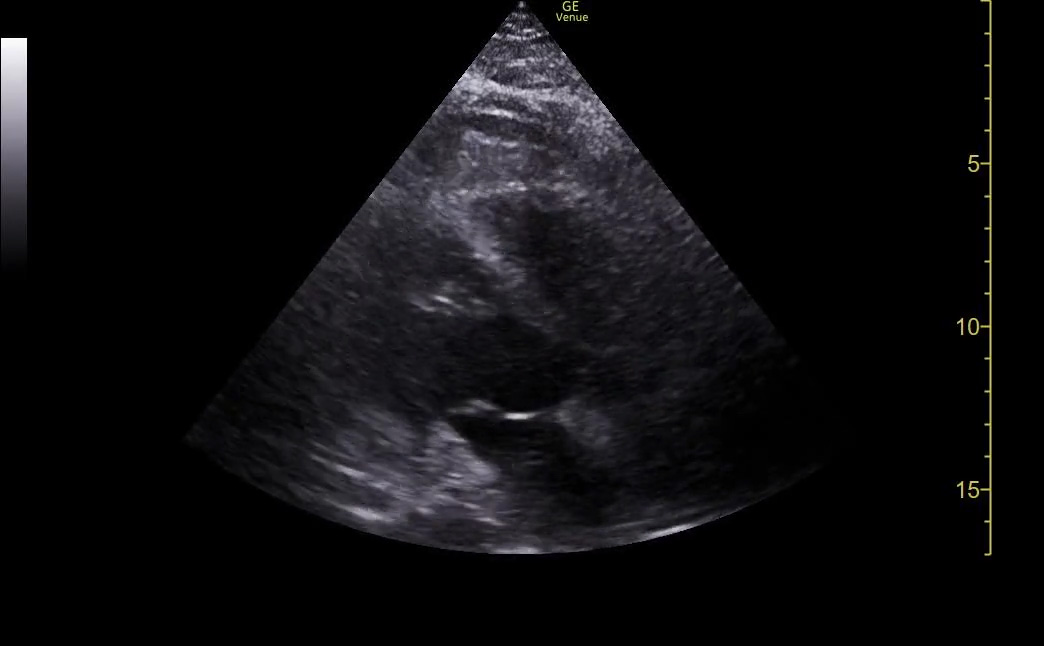

Too much depth

The problem with too much depth is that it wastes screen space. The machine has to use computing power to fill every pixel on the image. Every pixel that is used for something other than the AOI is wasted space. That means less of the screen is filled by the area of interest.